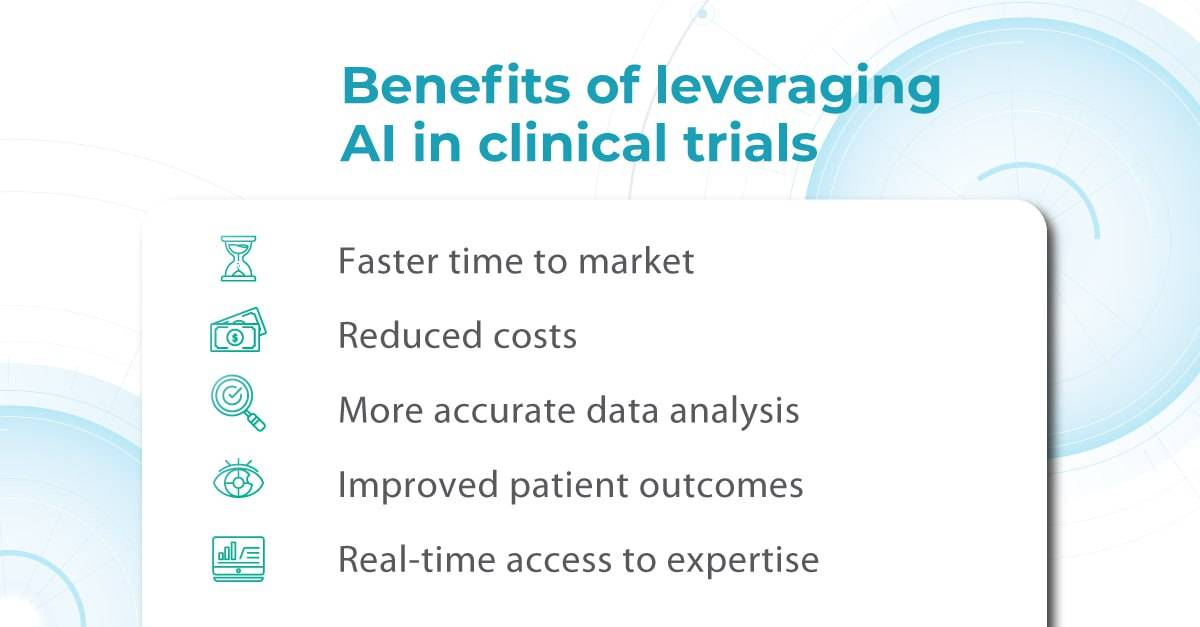

Here is where AI enters the game. With its ability to rapidly analyze vast amounts of data and detect subtle patterns, AI is revolutionizing how we approach clinical trials for ophthalmic drugs.

AI can automate this process, rapidly analyzing medical imaging and extracting relevant information to determine patient eligibility. This reduces the burden on staff and allows for faster identification and enrollment of suitable participants, streamlining patient selection and ultimately leading to more efficient and successful clinical trials.

A targeted approach can dramatically improve recruitment efficiency by pinpointing ideal candidates and even revealing disease hotspots for geographically focused efforts.

In later phases of clinical trials (Phase II and III), AI-powered image analysis can also play a pivotal role. In ophthalmology, AI can analyze OCT scans to precisely quantify disease biomarkers, ensuring that the trial participants are those most likely to benefit from the investigated drug. This improves the success rate of trials and minimizes potential harm to patients who might not be suitable candidates.

AI-powered image analysis offers a crucial advantage: reducing variability in interpretation.

AI algorithms can standardize the imaging overview process by consistently identifying and quantifying key biomarkers, ensuring that different readers arrive at similar conclusions.

Artificial intelligence has the potential to significantly impact drug discovery by enabling more creative and efficient experimentation. It can also reduce the cost and time associated with failures throughout the drug development process. By identifying promising leads earlier and eliminating less viable options, AI can streamline each stage, potentially halving the total cost of a single project.

Advanced simulation and modeling techniques powered by AI are also poised to revolutionize our understanding of disease mechanisms and accelerate the discovery of new drugs.

The promising potential of AI in clinical trials extends to the proactive identification and mitigation of adverse events, enhancing patient safety and reducing trial risks. Data-driven AI tools are poised to revolutionize the entire clinical trial process, from design to execution. By streamlining patient recruitment, continuously monitoring participants, and facilitating comprehensive data analysis, AI can increase trial success rates, improve adherence, and yield more reliable endpoints.

The future of ophthalmic drug trials is here, and it’s powered by AI. By embracing this technology, researchers and clinicians can unlock new possibilities for preventing blindness and preserving vision for future generations.